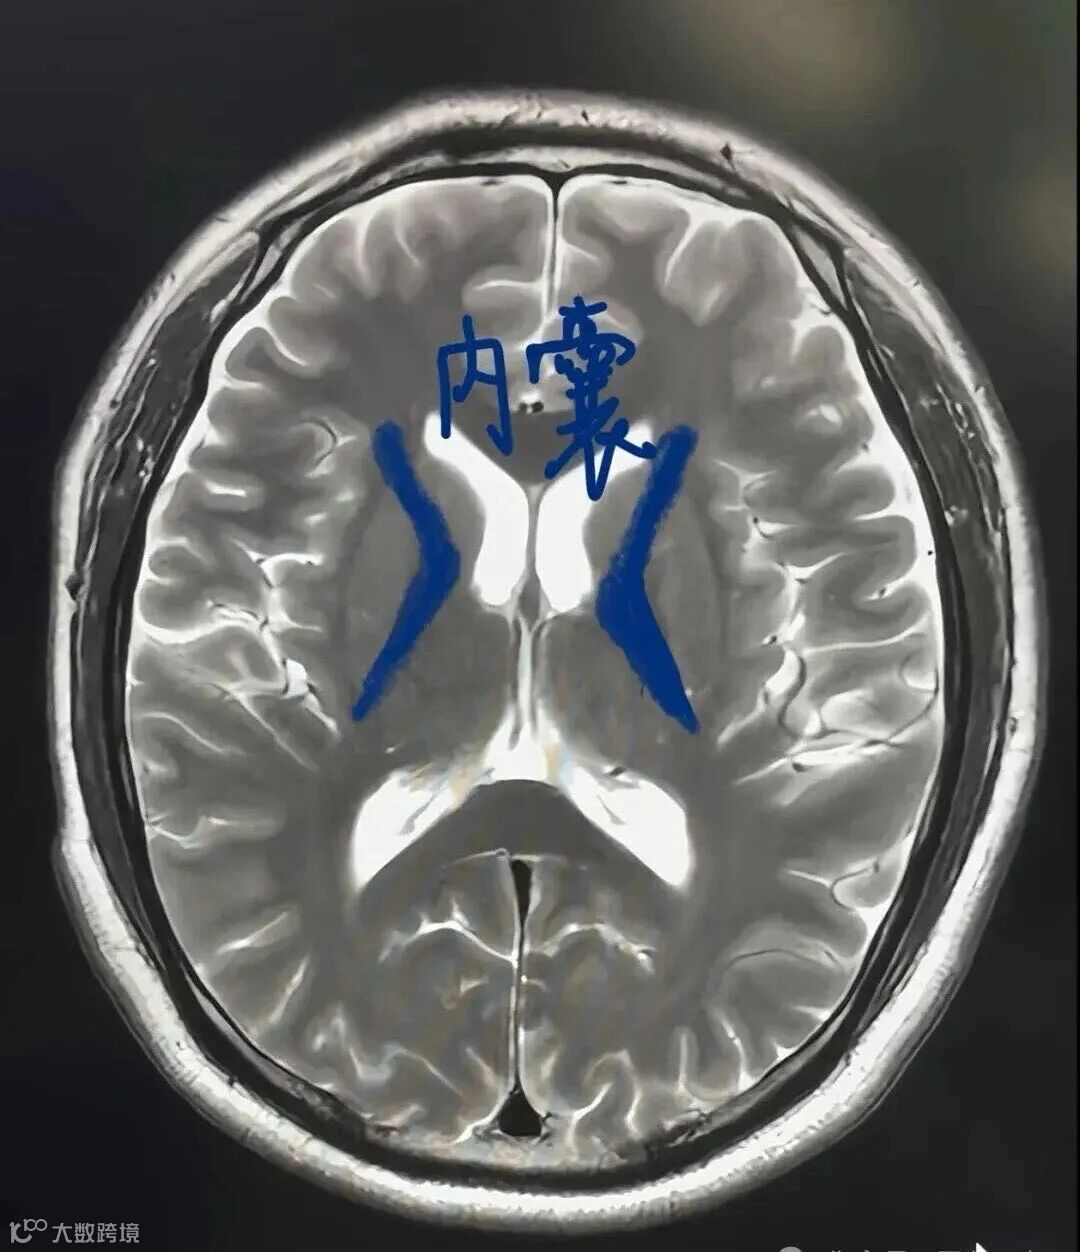

放射冠:指两侧侧脑室周围的脑白质层面。